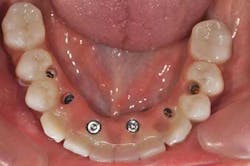

Fig. 11: For a better prosthetic outcome, the implants in site 26 and 27 have been extracted and replaced with two Biomet 3i® implants.

Fig. 12: A new implant impression is taken

Fig. 13a, b: The new master cast shows the modified implant situation